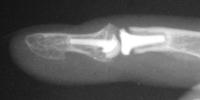

The trial implant sizer shows the true size of the implant. The final implant has a radiolucent coating  which makes it appear smaller than it is on Xray.

Final implant radiographs.